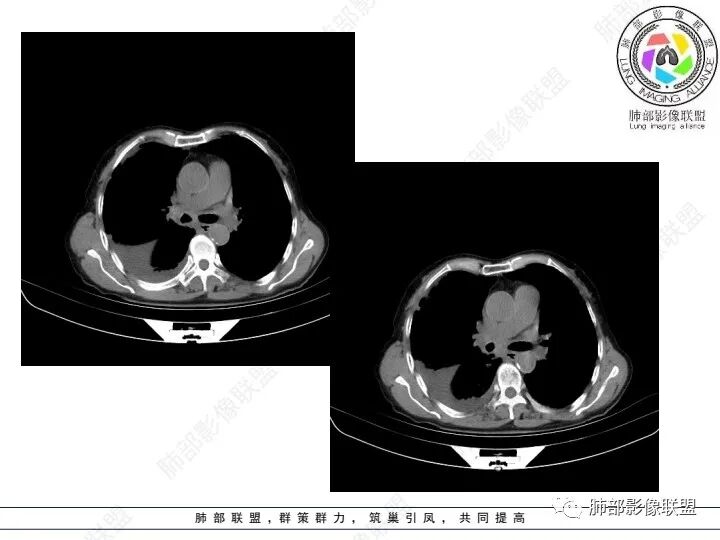

老年女性,肺气肿。腹痛、便血入院。Ca125明显增高。

右肺下叶类圆形软组织密度影,纵隔及肺门多发肿大淋巴结、有融合,右下肺支气管壁增厚伴环形钙化、狭窄,右侧胸膜见结节灶,增强后均匀明显强化;右侧胸腔积液。考虑:右肺下叶肿瘤伴纵隔肺门、胸膜转移,考虑腺癌可能。

女,69,腹痛、便血4小时。CA125增高。胸部CT:肺气肿背景。右下叶不规则肿块影,处于外周气肿带与正常肺交界区,强化不均匀,中心有坏死;纵隔及肺门多发肿大淋巴结、融合,包绕支气管,部分钙化、环形强化;右下支气管周围管壁增厚伴环形钙化、狭窄。右侧胸膜多发结节灶,增强后明显强化,右侧胸腔积液。考虑恶性,右下肺腺Ca多发转移?转移瘤?鉴别TB、IgG4等。

4、综上,老年男性,CA125升高,右肺下叶肿块侵犯胸壁,伴纵隔、右肺门及纵隔淋巴结肿大,右侧胸腔积液、胸膜增厚伴结节影,强化明显,应该为一较典型的肺癌伴肺胸膜腔及肺门纵隔淋巴结转移,尤其是肺腺癌。

几个细节值得留意:

1)由肺内侵及胸壁的块影,即提示其恶性生物学行为,也不为转移灶所常见。

2)右肺下叶肿块,右肺门及纵膈未见肿大淋巴结,符合肺癌迁徙途径。

3)转移瘤较少直接侵犯支气管。不是没有,如肾透明细胞癌转移或晚期无差别攻击,但总体较少。

4)转移灶多发但均限于右侧胸腔内,一般不符合远道而来的“双侧”。无论该患者有无腹腔或其他部位原发病灶。